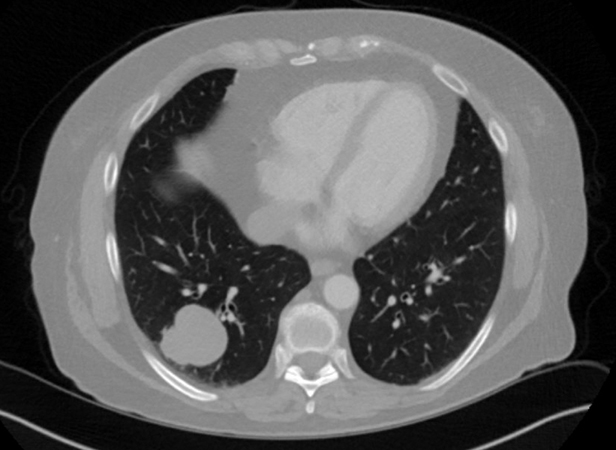

Clinical History:A 74-year-old woman, never smoker, with no significant past medical history, was found to have an incidental left upper lobe lung nodule following a fall. The lesion showed progressive growth, and a biopsy was performed (see Figures 1 through 6).

On imaging, primary pulmonary ES is generally a solitary well-circumscribed mass. They often have a heterogenous appearance, due to the necrosis and hemorrhage associated with these tumors. In general, extraskeletal ES should not have an osseous component and, in primary pulmonary ES, calcification is rare. Because the lung is the most common site of ES metastasis, it is critical to exclude a skeletal primary.